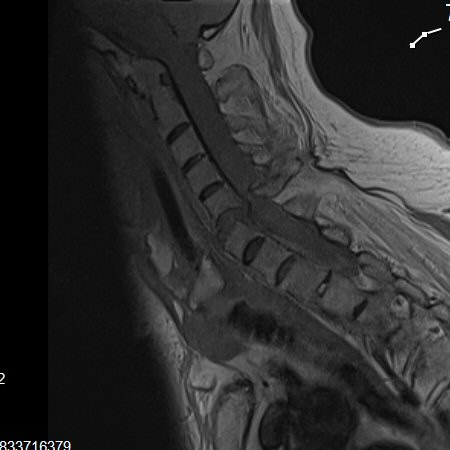

Notera att vid Bechterews sjukdom eller DISH-förändringar så blir frakturer ofta instabila. MR-undersökning krävs ofta inför operationsbeslut.

Instabil fraktur mellan C5 och C6 i Bechterew-rygg där ryggmärgen kapats nästan helt.

Fraktur i DISH-rygg mellan C2-C3 och C3-C4. Tetraplegisk.